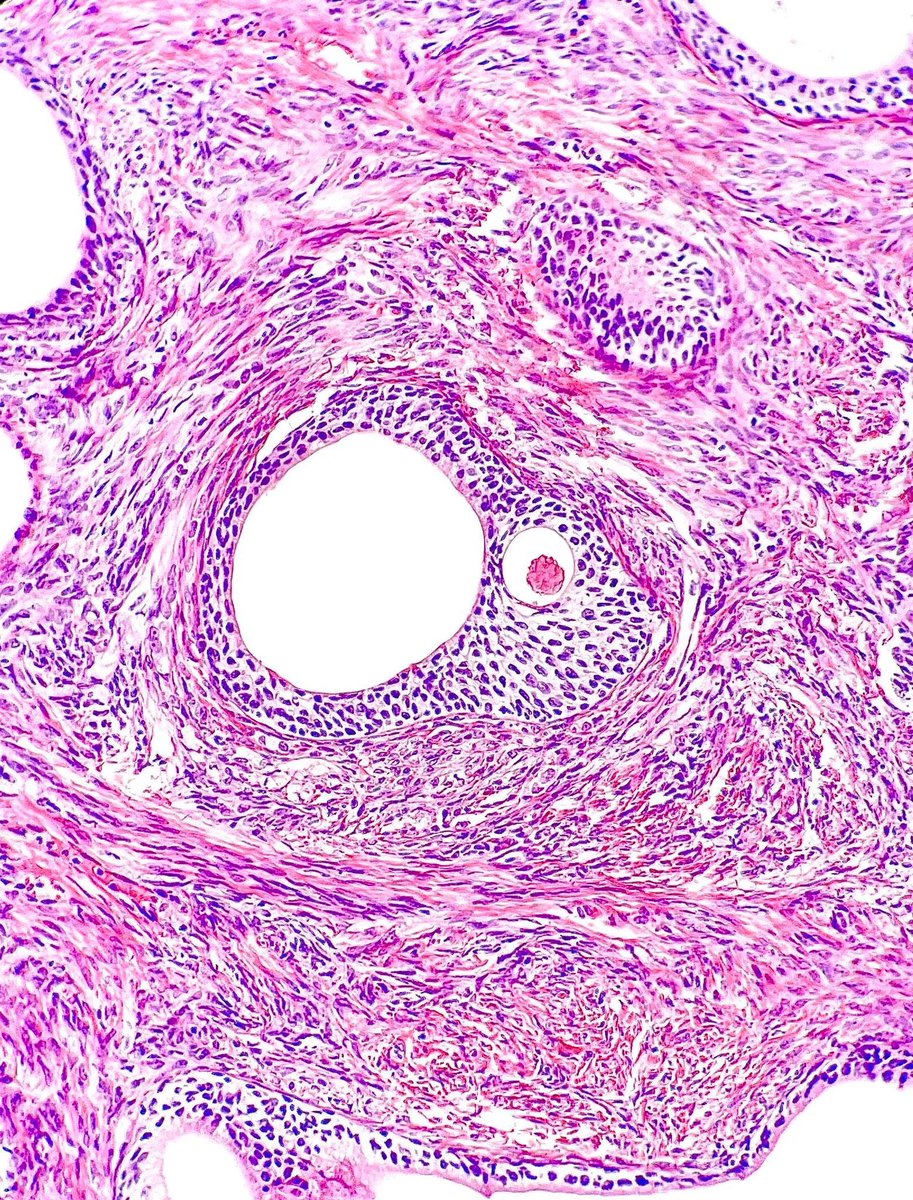

@Gloria_SuraMD

Gloria Sura, MD

3 days

Nephrectomy specimen revealing small cuboidal cells are seen arranged in a single layer around papillary cores containing foamy macrophages. What tumor is this? Answer: https://t.co/E0xAZaHCR8 #PathArt #PathTwitter #Cytopath #Pathology

4

21

89